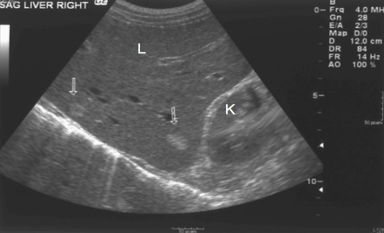

What is the kidney’s echogenicity to the liver?

Isoechoic

The liver contains two areas (arrows) that are ____________ compared with the rest of the echogenicity of the liver

hyperechoic